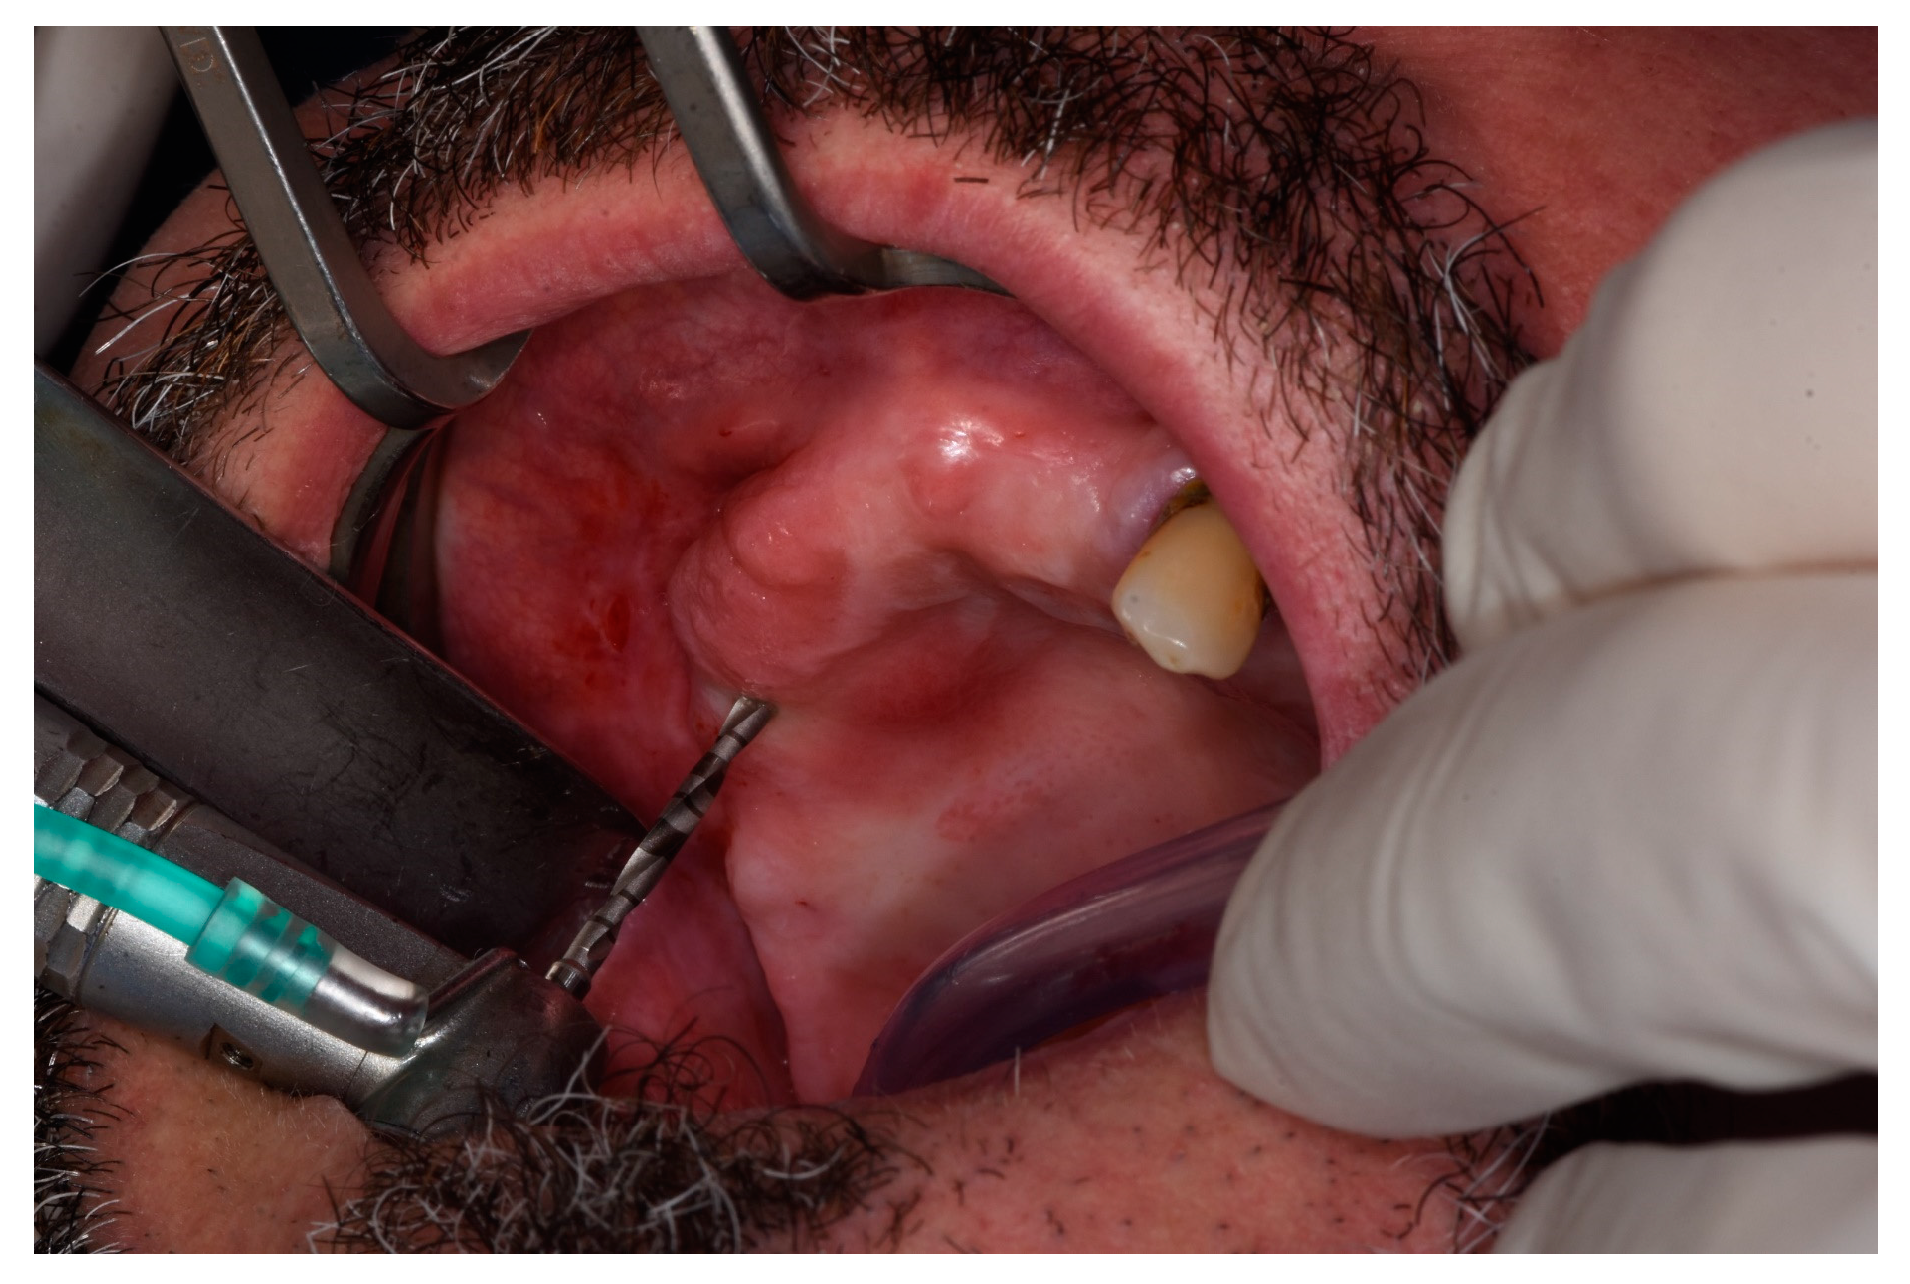

2.2. Surgical Procedures and Post-Operative Care